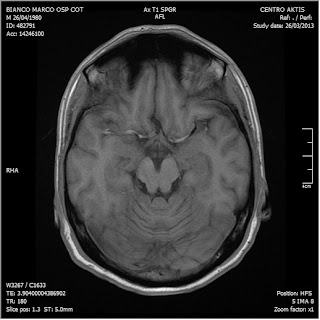

26/03/2013. Ritorna a controllo al Cotugno dove effettua nuova RM con MdC

RM del 26/3/2013